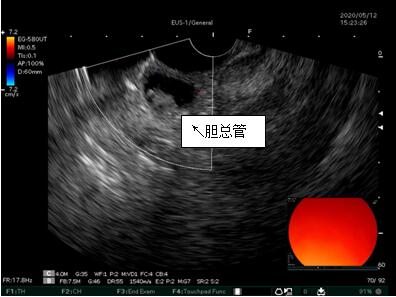

69歲王姓患者,因“發(fā)現(xiàn)無(wú)痛性黃疸1月”入院,根據(jù)患者病史,患者診斷傾向于壺腹部腫瘤所致梗阻性黃疸。予以完善腹部CT及上腹部MRI加MRCP均顯示肝內(nèi)外膽管擴(kuò)張,未發(fā)現(xiàn)明顯膽管,胰腺及十二指腸乳頭部腫瘤,且患者CA199正常。以前醫(yī)院未引進(jìn)超聲內(nèi)鏡,這類患者到此就遇到診斷瓶頸。此患者經(jīng)過消化內(nèi)科張丹霞副主任醫(yī)師完善超聲內(nèi)鏡檢查后,可以清楚顯示膽總管下段壁內(nèi)軟組織占位?;颊咄ㄟ^超聲內(nèi)鏡檢查診斷明確,轉(zhuǎn)至肝膽外科行手術(shù)治療。

超聲胃鏡圖片

膽總管小腫瘤性病變CT及MRI檢查陽(yáng)性率偏低,因其低代謝特征,PET-CT陽(yáng)性率也偏低,超聲內(nèi)鏡對(duì)這類疾病的診斷陽(yáng)性率是所有檢查中最高的,且可行穿刺活檢進(jìn)一步確診病灶性質(zhì)。

環(huán)掃超聲內(nèi)鏡主要用于胃腸道粘膜下腫物診斷,胃腸道腫瘤分期,發(fā)現(xiàn)早期胃癌等,扇掃超聲內(nèi)鏡主要用于診斷膽道及胰腺疾病,并且可行穿刺活檢取病理。